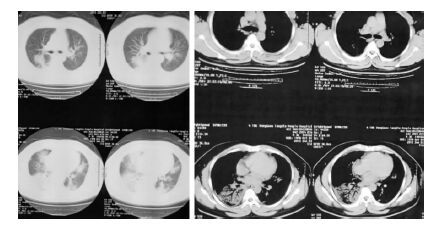

1 资料与方法 1.1 一般资料患者,男,36岁,因“发热、咳嗽1周,加重伴气促半天。”于2015年1月5日由外院转入东莞市人民医院急诊科。患者1周前淋雨后出现发热,最高体温39.7 ℃,随后出现咳嗽、咳黄白色黏痰,至当地小诊所就医,予对症、抗生素等治疗,无好转。发病后第4天,至当地中心医院住院,按肺炎予抗感染、抗病毒(口服奥司他韦75 mg,Q12 h)、祛痰等治疗。半天前,患者上述症状加重,伴气促、咯大量淡红色稀痰,急送至本院急诊科。拟“重症肺炎;呼吸衰竭”收入ICU。既往史:有“乙肝病毒携带者(小三阳)”病史,未定期复查。个人史:患者在菜市场内经营粮油店,离活禽宰杀点约50 m,家属否认直接活禽接触史。查体:T 37.2 ℃,R 45次/min,P 136次/min,BP 135/74 mmHg(1 mmHg=0.133 kPa),SpO2 37%,神志模糊,烦躁不安,呼吸急促,口唇发绀,气管居中,双肺呼吸音粗,满布湿啰音。心率136次/min,律齐,各瓣膜听诊区未闻病理性杂音。腹软,无压痛,无反跳痛。双下肢无浮肿。血常规:WBC 7.46×109 L-1,NE 6.45×109 L-1,LY 0.54×109 L-1,B型尿钠肽(BNP) 40.4 pg/mL(参考值:0~73 pg/mL),降钙素原(PCT) 1.48ng/mL(参考值:<0.05 ng/mL),凝血功能:PT 14.5 s,INR 1.13,APTT 45.2 s,Fib 4.84 g/L,TT 20.9 s;D-二聚体 6.82 μg/mL,肌红蛋白 462.8 ng/mL,肌钙蛋白 0.043 ng/mL,PaO2 51 mmHg,OI 51 mmHg,LDH 811.5 U/L(参考值:114~200 U/L)。发病后第4天的胸部CT见图 1,第7天的胸片见图 2。入院后送取标行病毒核酸检查为阳性,标本送至市级和省级疾控中心复查,均报告为H7N9禽流感病毒核酸检测阳性。诊断:(1)人感染H7N9禽流感病毒(重型);(2)重度ARDS。

| 图 1 发病第4天的胸部CT |

该病例的临床特点为年轻男性,有可疑活禽接触史,起病以发热、咳嗽等症状为主,病情发展迅速,起病一周后迅速发展为严重ARDS,需启用体外膜肺氧合(extracorporeal membrane oxygenation,ECMO)支持。按Gao等[2]总结的2013年中国内地111例H7N9禽流感病例临床特征分析,多数患者以发热咳嗽为主要症状,发展为中重度ARDS的患者一般具有65岁以上、有合并症、淋巴细胞计数减少、CK和AST升高、使用神经氨酸酶抑制剂不及时等因素有关。此病例除年龄因素外,其余各个条件均符合以上危险因素,特别是过迟和不足量使用神经氨酸酶抑制剂可能是病情迅速加重的重要原因。另一个突出的症状是大量水样痰,这可能是肺损伤发展到非常严重状态下的一种表现,病毒诱导的全身炎症反应失控造成肺毛细血管损伤,渗透性显著增加,出现严重肺水肿和ARDS。